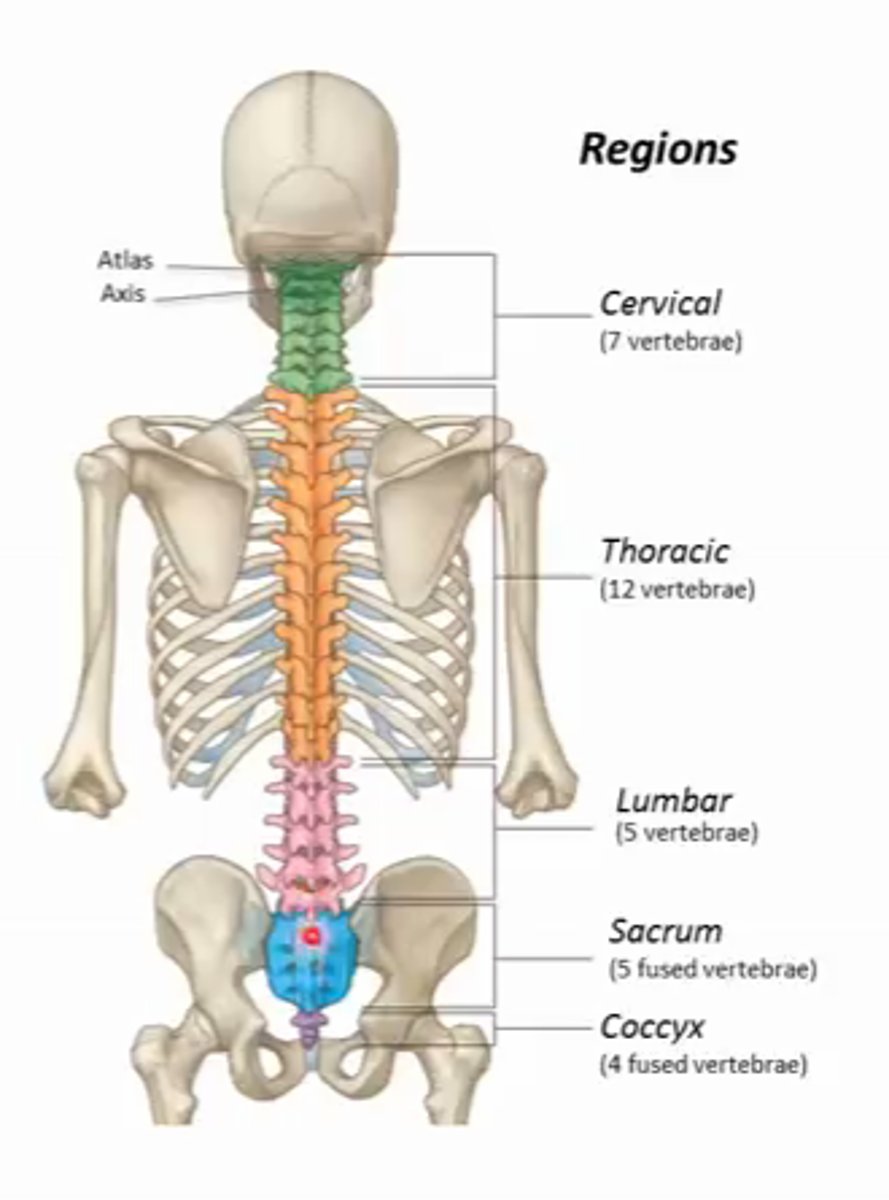

7

How many vertebraes are in the cervical area?

12

how many vertebraes are in the thoracic area?

5

how many vertebreas are in the lumbar area?